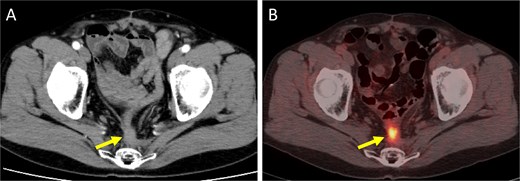

A 52-year-old man underwent emergency Hartmann’s procedure for peritonitis caused by perforated sigmoid colon cancer. The tumor was staged as pT4b N0 M0 with no lymphovascular invasion. Postoperative examination revealed synchronous advanced lower rectal cancer. Systemic chemotherapy with mFOLFOX6 plus bevacizumab was administered, followed by neoadjuvant chemoradiotherapy and abdominoperineal resection. Pathological examination confirmed pT3 N0 M0 disease, with no lymphovascular invasion. A total of 2 years and 4 months after the initial surgery, a solitary lung metastasis appeared and was surgically resected. Three years after the initial surgery, imaging revealed LRRC on the anterior surface of the sacrum (Fig. 1). Given the history of multiple laparotomies and treatment for distant metastases, surgical resection was considered inappropriate. After thorough consultation with a CIRT facility and the patient, a plan was made to perform CIRT followed by prophylactic resection of the adjacent irradiated small intestine that was thought to be at a high risk of causing ulcers and perforation. CIRT was administered using carbon ion beams at a dose of 70.4 Gy (relative biological effectiveness weighted dose) in 16 fractions over 4 weeks (Fig. 2). Three months after completion of CIRT, the irradiated small intestine, including a 30-cm segment adherent to the recurrent site, was prophylactically resected (Fig. 3A and B). The serosal surface appeared intact (Fig. 3C), and observation using indocyanine green (ICG) fluorescence imaging indicated good blood flow (Fig. 3D). However, the mucosal surface showed ulcer formation near the adhesion site (Fig. 4). Histopathologically, the ulcerated areas showed necrosis at the ulcer base surface and transmural infiltration of inflammatory cells (Fig. 5). The postoperative course was uneventful, and the patient has remained recurrence-free for 2.5 years.

Imaging findings at the time of local recurrence diagnosis. (A) Contrast-enhanced CT. (B) Positron emission tomography-CT. Arrows indicate the recurrent lesion.